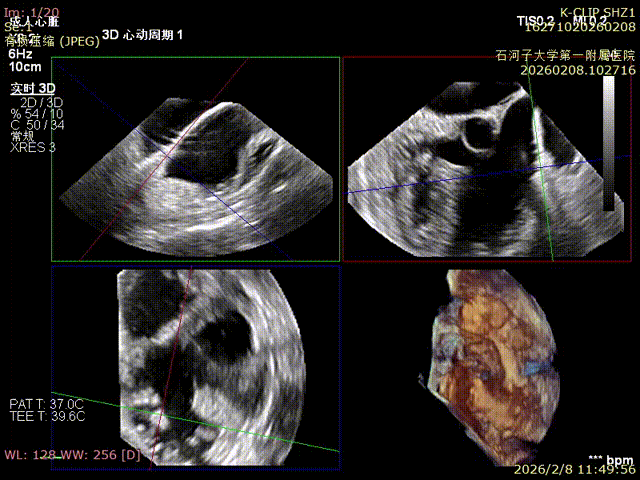

Preoperative anteroseptal regurgitation

Preoperative 3D view of regurgitation

Preoperative TTE: 4-chamber view regurgitation

Immediate Postoperative Echocardiographic Assessment: Tricuspid regurgitation was reduced from preoperative grade 4+ to grade 1+, the annulus diameter was reduced to 6.15 cm², and the leaflet coaptation was satisfactory.

Preoperative annulus area: 11.5 cm²

Postoperative annulus area: 6.15 cm²